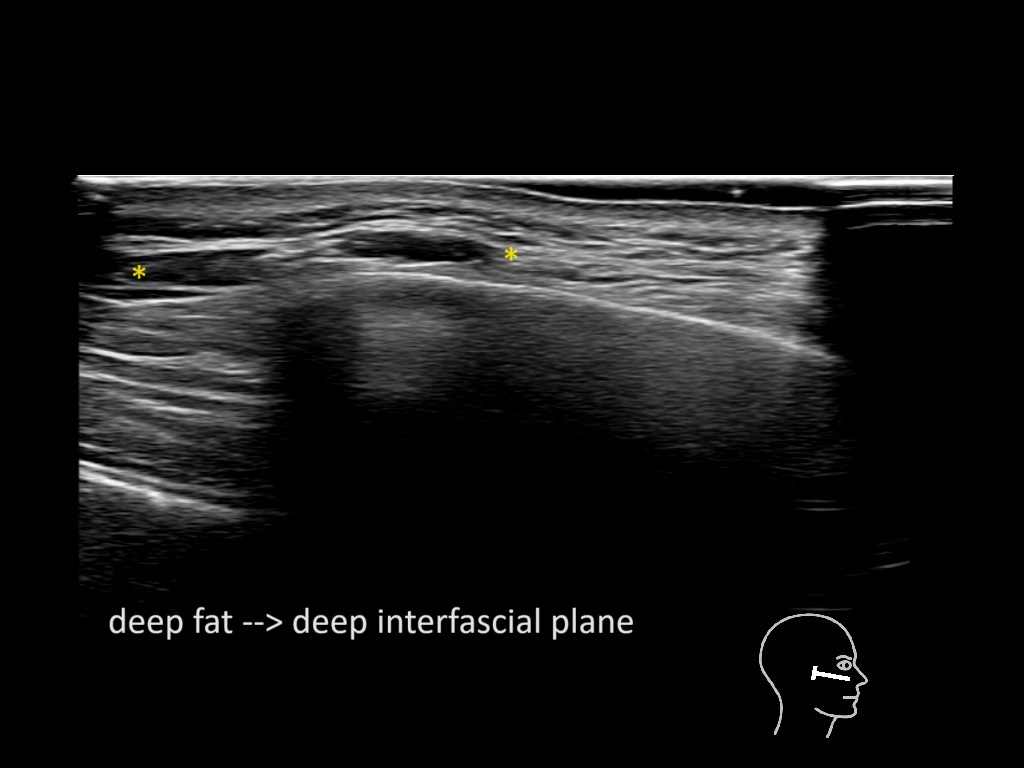

Filler behavior - Temple zygoma US

Study the first image to recognize the different layers. If you are sure about the layers, swipe to the second image to view the answer (if applicable).